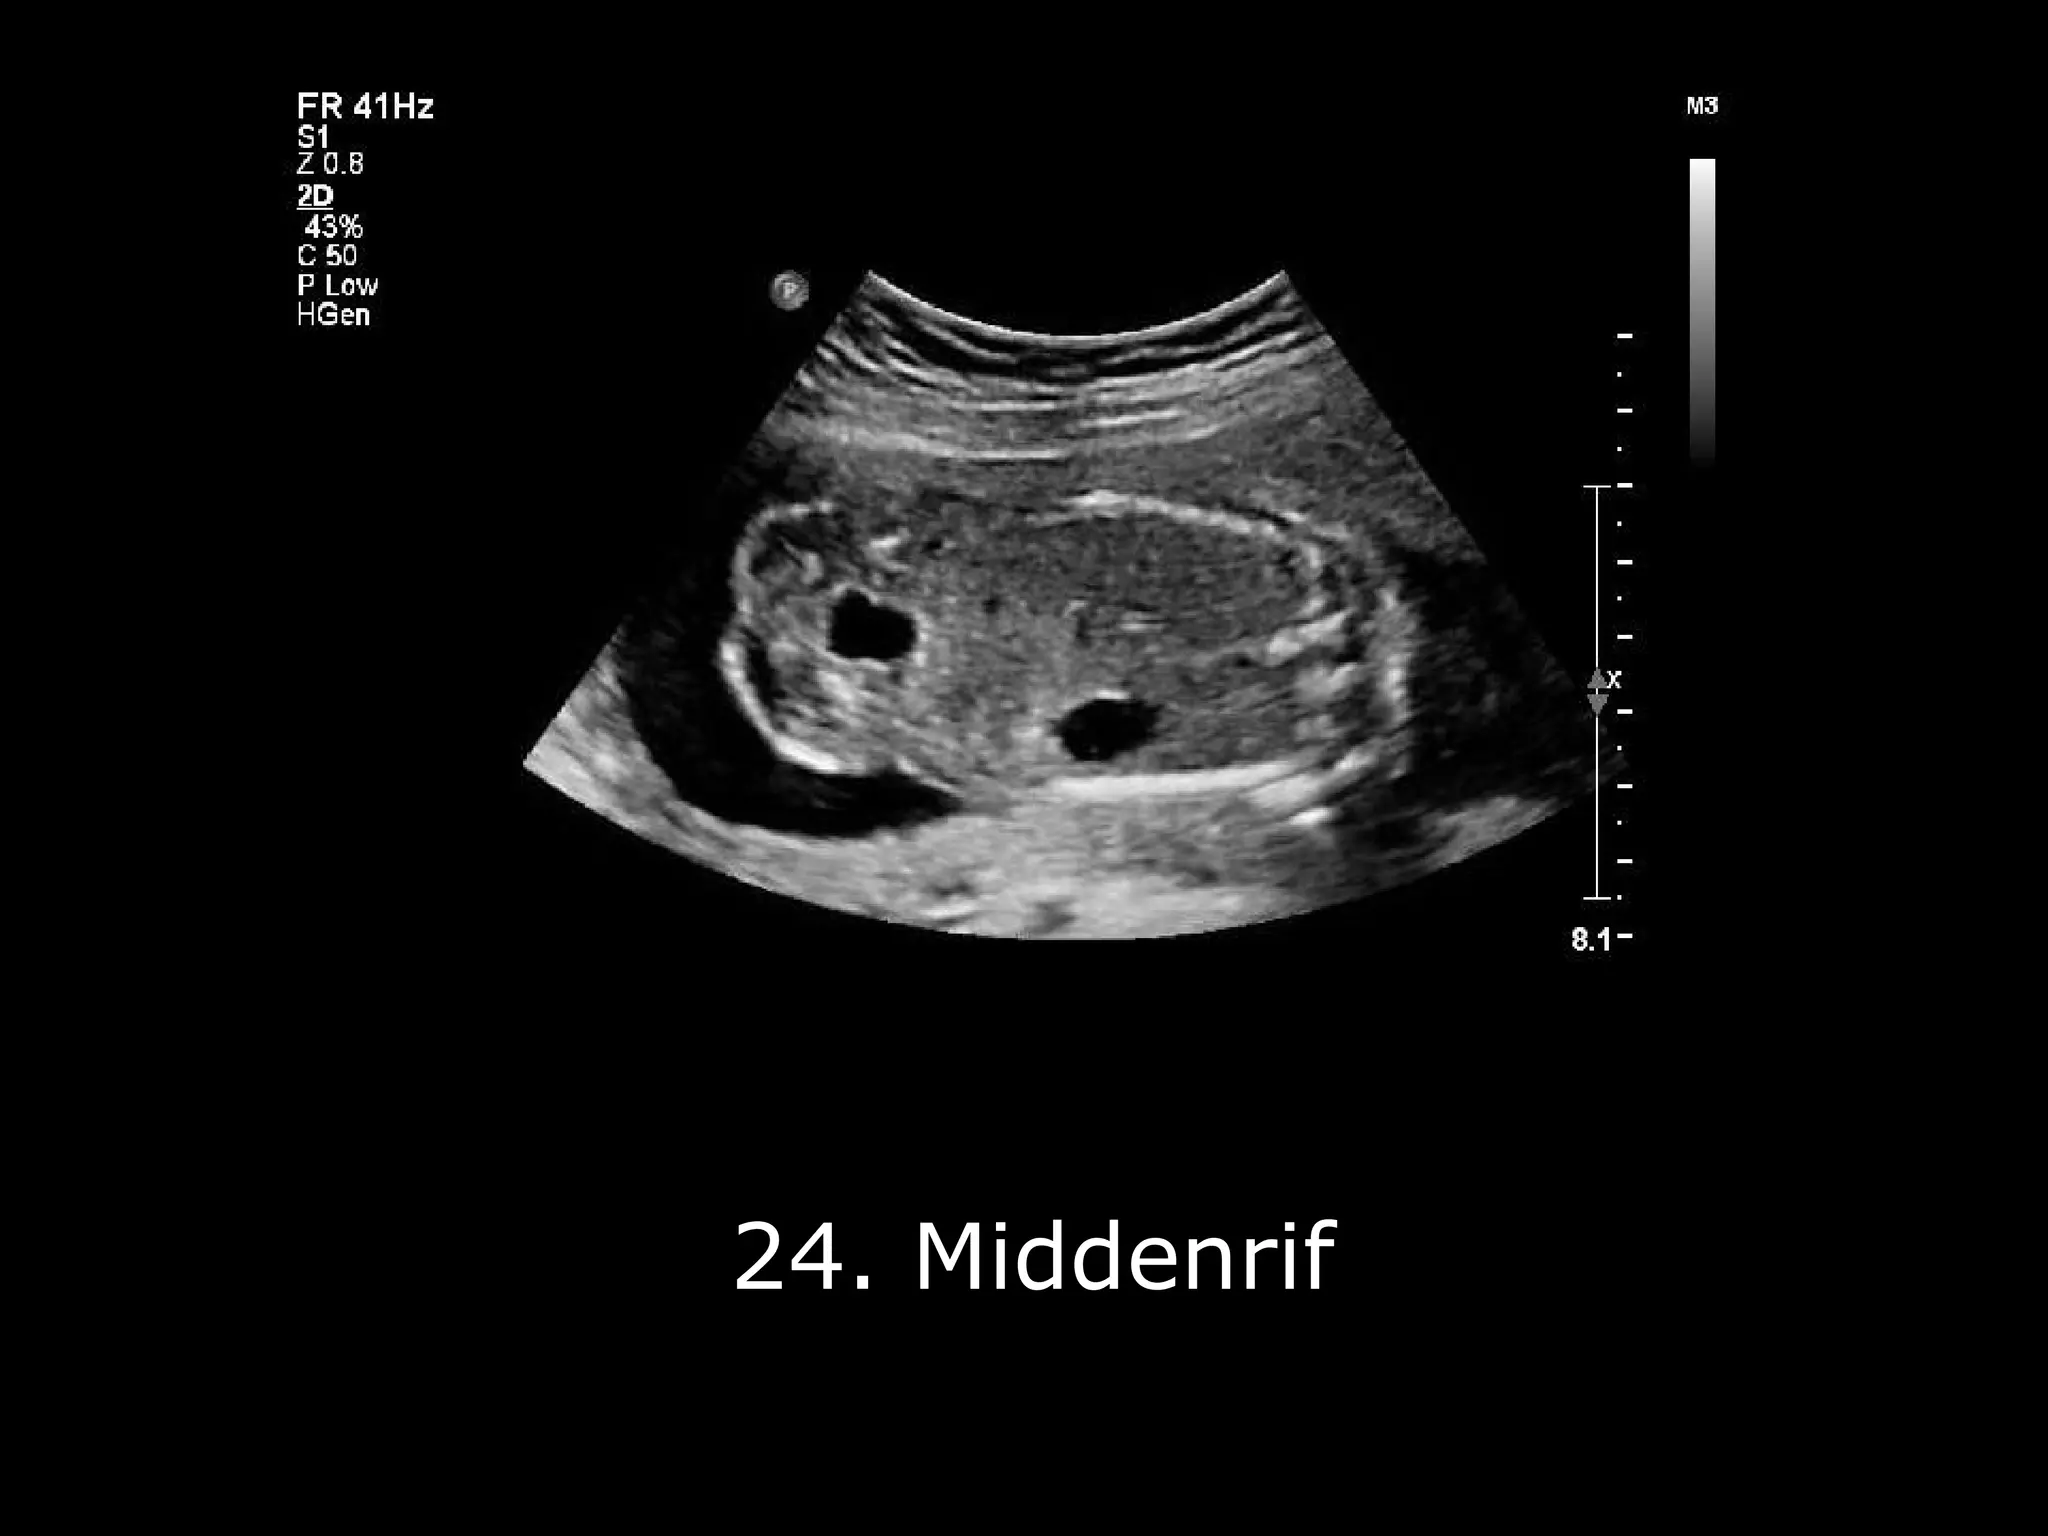

De 20-weken echo, ook wel de Structureel Echoscopisch Onderzoek (SEO) genoemd (moeilijk woord, hè?), is een uitgebreide check-up voor je baby. Zie het als een APK-keuring, maar dan voor een piepklein mensje in wording. Ze kijken echt alles na: de hersenen, het hartje, de niertjes, de ruggengraat... noem maar op!

Het is echt fascinerend om te zien. Alsof je een glimp opvangt van een geheim. En de echoscopist (wat een woord hè, net een goochelaar) is er om alles uit te leggen. Ze wijzen aan waar de beentjes zitten, of het hartje goed klopt (boem boem!), en of alles eruitziet zoals het hoort.

Maar... (ja, er is een 'maar') een EBV kan in sommige gevallen geassocieerd zijn met andere afwijkingen. Daarom is het belangrijk dat de echoscopist extra goed kijkt tijdens de 20-weken echo. Ze zullen extra aandacht besteden aan het hartje, de nieren en andere organen om er zeker van te zijn dat alles er goed uitziet.